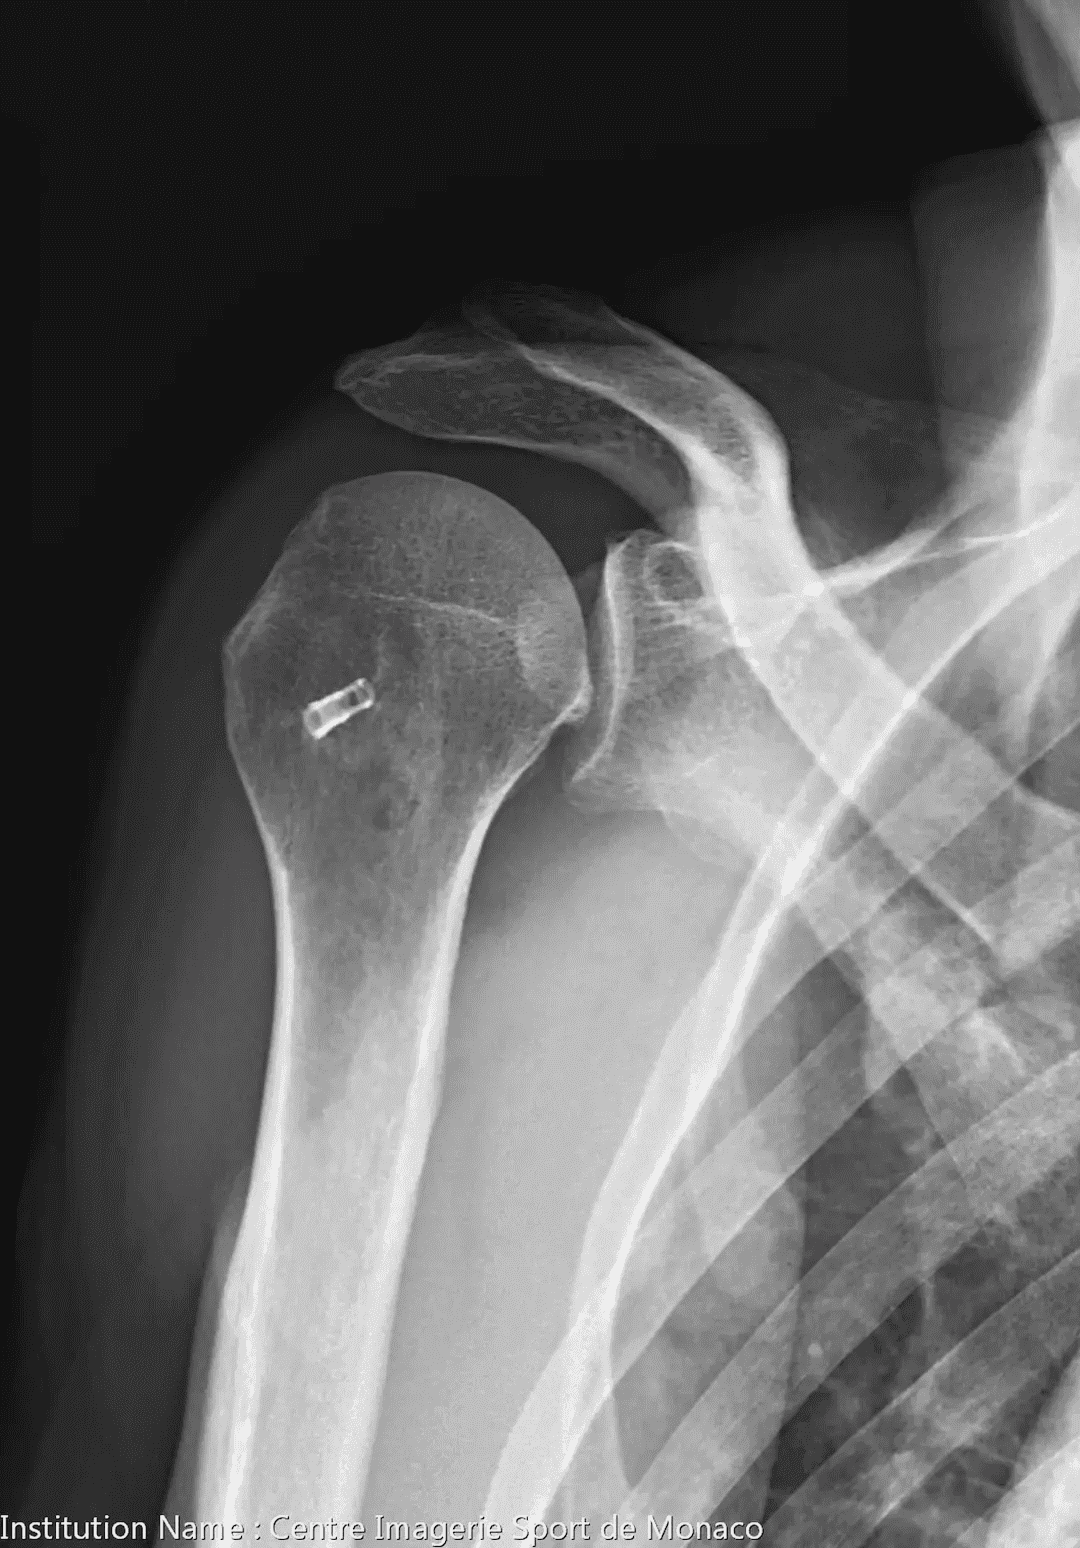

Radiographie

Discrète atteinte dégénérative de l'articulation gléno-humérale.

Pas d'ascension de la tête humérale